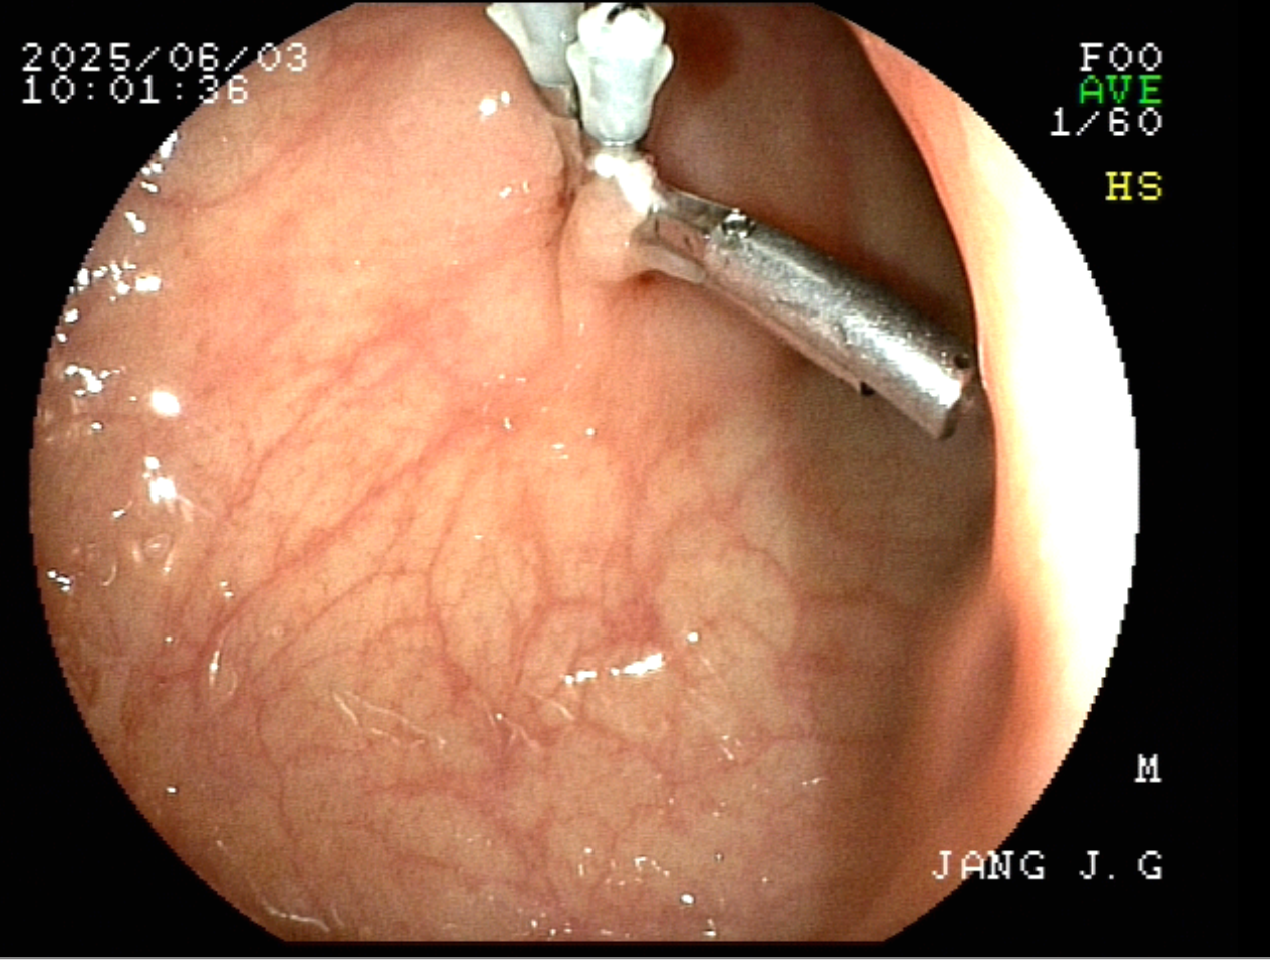

76세 남자 검진 대장 내시경시 발견된 1.0cm LST type 의 EMR(점막절제술)의 실제례

1. 구불대장에 1.0cm LST type(평탄한 형태)의 용종이 관찰된다.

4. 올가미 용종 절제술후의 점막 모습이 관찰된다.

5. 절제된 점막면을 4개의 클립으로 결찰술후 안전하게 용종 절제술을 마무리 합니다.